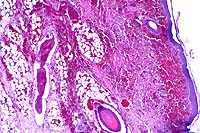

4x

obj

40x

- Case 7-1. Dermis. The 4x view demonstrates a

thrombus within a valved vein (left of center). The dermal connective

tissue is expanded by hemorrhage beneath the epidermis and around

blood vessels. The 40x view shows the thrombus and vessel wall

in which there are vague outlines of bacilli.